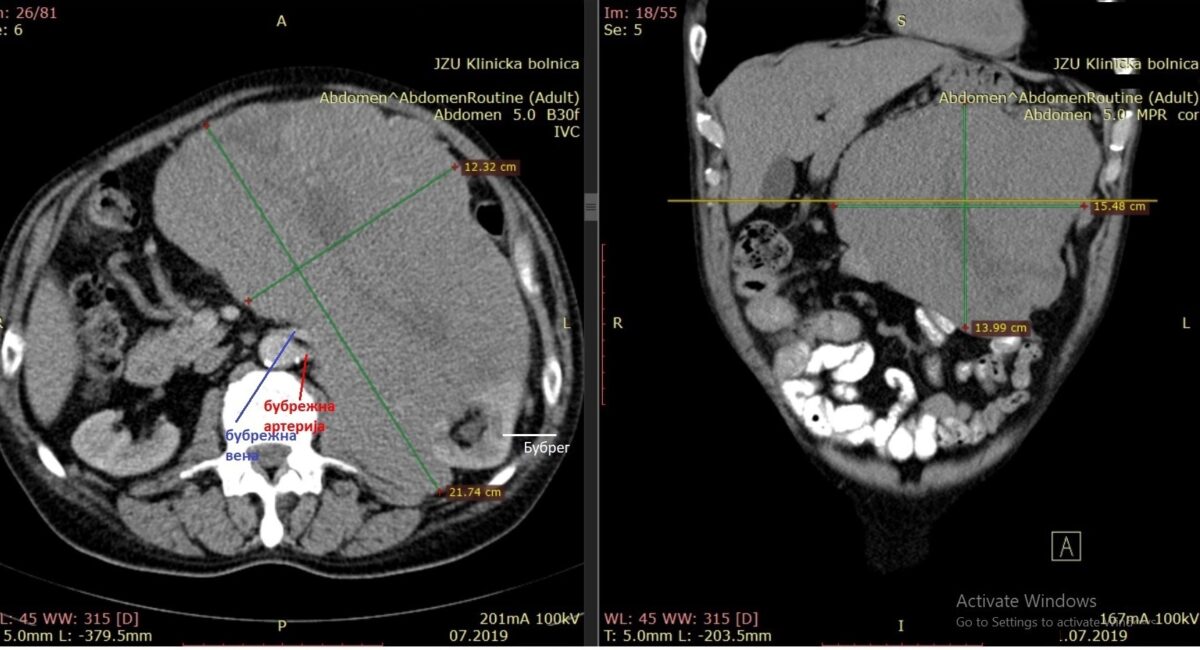

– Констатирано е дека пациентот на возраст од 71 година има неврофибросарком во левата страна во ретроперитонеум. При клинички преглед утврден е голем палпабилен тумор во абдоменот, кој јасно се испакнува. Исто така, беше видлива рана од претходна биопсија. Лабораторијата беше во прилог на неконтролирана гликемија, анемија, тромбоцитоза, потхранетост. Проверката на МСКТ покажа дека туморот го инфилтрира левиот бубрег и неговите крвни садови, го избуткува колонот и има нејасен однос кон мезентерични крвни садови од тенкото црево. Истовремено го истуркува/инфилтрира панкреасот и прави компресија на лиеналната вена. Поради анемијата и потхранетоста, подготовката за оперативен третман е направена согласно ERAS (Enhanced Recovery After Surgery) протоколот – информира проф. д-р Милчо Пановски, абдоминален хирург, супспецијалист во „Жан Митрев“.